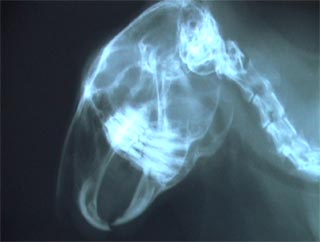

○ウサギの臼歯の咬合状態

下顎が狭く、上顎が広い

咬合面が頬側に低く、

舌側に高い傾斜状態である。

○常生歯型:

歯根は長く、根尖は常に開放している。

ウサギの臼歯は生涯を通じて伸び続ける。